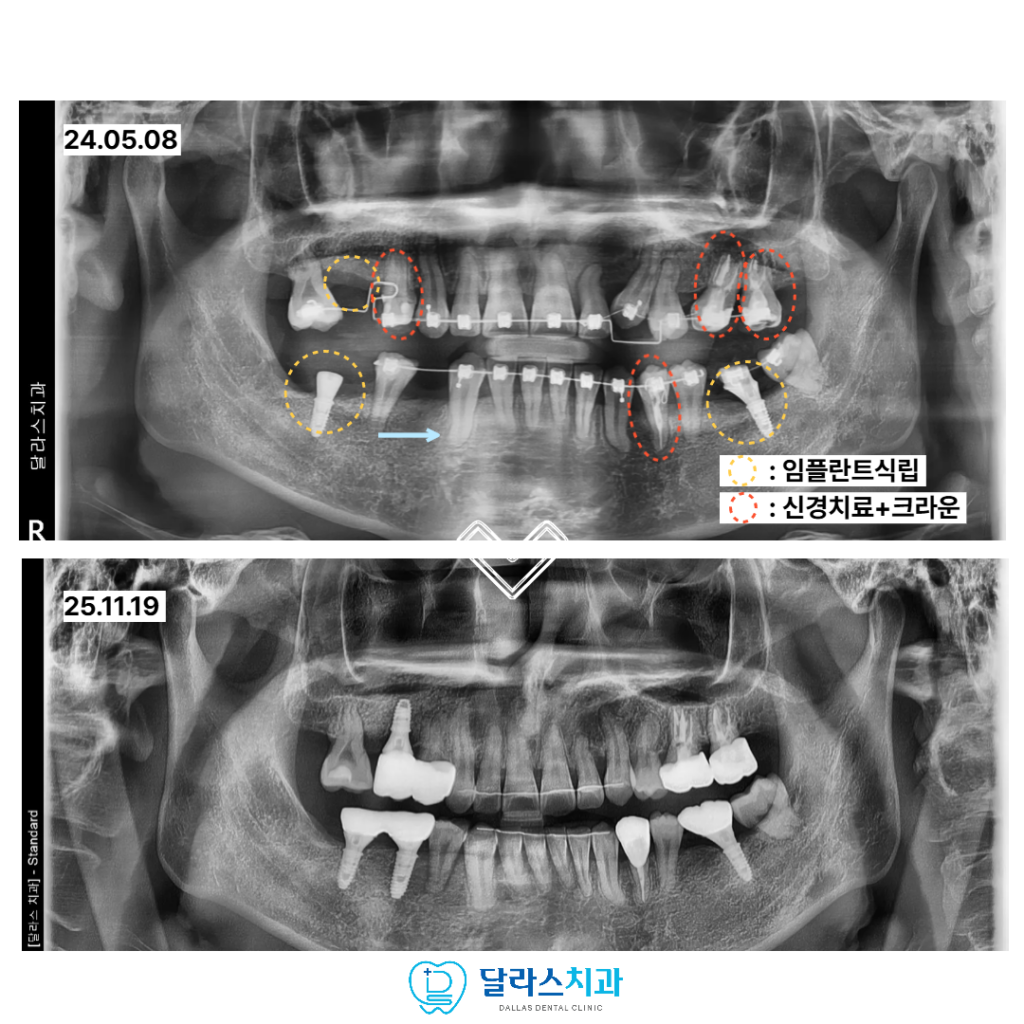

이번 환자분은 극심한 치과 공포증으로 인해

오랜 기간 치료를 미뤄오다 내원하신 30대 남성분이었습니다.

여러 치아가 충치로 손상되었거나 이미 발치된 상태였고

상실된 부위로 인해 어금니 교합이 되지 않으면서

입을 벌릴 때마다 옆에서 들릴 정도로 큰 소리가 나는 상황이었습니다.

이는 턱관절이 안정적인 위치를 잡지 못하고 있다는 신호로

전반적인 교합을 다시 정비해야 하는 상태였습니다.

초진 검사에서 앞니 쪽 치아가 심하게 겹쳐 있는 크라우딩이 확인되었고

아래 치아의 중심선도 틀어져 있어 단편적인 치료로는 진행이 어려운 상황이었습니다.

충분한 상담과 진단 끝에 꼭 필요한 범위 내에서 발치를 결정하고

교정 치료를 시작하였으며 동시에 임플란트 치료를 병행하는 계획을 세웠습니다.

노원치과 치료 과정에서는 어금니의 지지 역할을 회복하는 데 중점을 두어

교합을 안정적으로 만들어 주었고,

턱이 가장 편안한 위치에서 물릴 수 있도록

기준이 되는 교합 위치를 설정한 뒤 치료를 진행하였습니다.

또한 발치 치아를 가능한 줄이기 위해

아래쪽 사랑니를 교정적으로 이동시켜 새로운 교합 관계를 형성하였고

이를 통해 기능적인 균형을 보다 안정적으로 완성할 수 있었습니다.

총 치료기간은 약 2년으로,